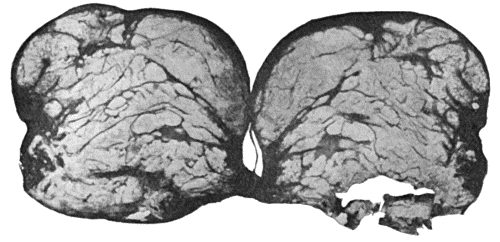

Fig. 2.—Staphylococcus aureus in Pus from case of Osteomyelitis. × 1000 diam. Gram's stain.

Staphylococcus Aureus.—This is the commonest organism found in localised inflammatory and suppurative conditions. It varies greatly in its virulence, and is found in such widely different conditions as skin pustules, boils, carbuncles, and some acute inflammations of bone. As seen by the microscope it occurs in grape-like clusters, fission of the individual cells taking place irregularly (Fig. 2). When grown in artificial media, the colonies assume an orange-yellow colour—hence the name aureus. It is of high vitality and resists more prolonged exposure to high temperatures than most non-sporing bacteria. It is capable of lying latent in the tissues for long periods, for example, in the marrow of long bones, and of again becoming active and causing a fresh outbreak of suppuration. This organism is widely distributed: it is found on the skin, in the mouth, and in other situations in the body, and as it is present in the dust of the air and on all objects upon which dust has settled, it is a continual source of infection unless means are taken to exclude it from wounds.